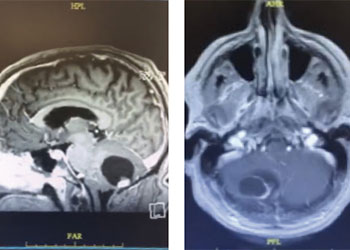

Brain:

Neurosurgeons Collaborate to Treat Giant Symptomatic Meningioma

Pineal Region Meningioma

Author: Michael Brisman M.D., F.A.C.S., Read More!